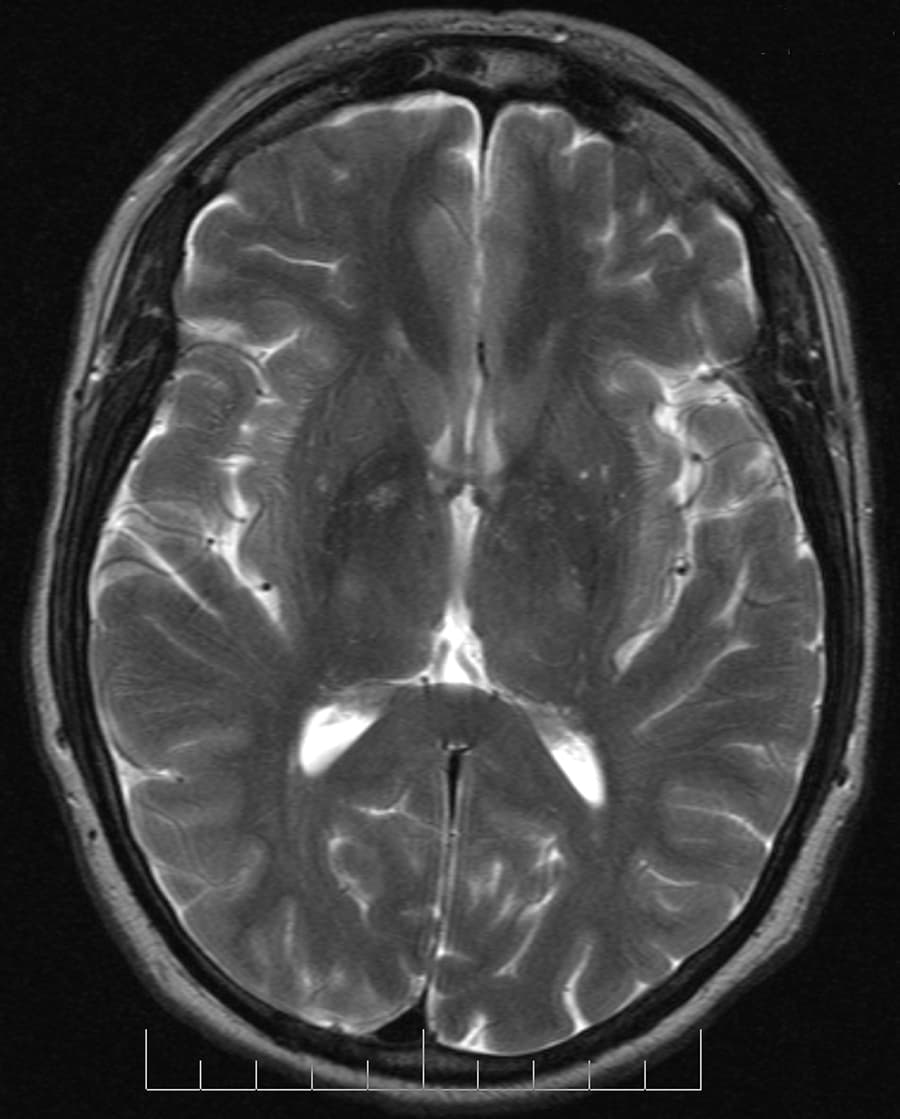

En neurosciences, la tractographie est une méthode utilisée pour mettre en évidence les voies neuronales. Elle utilise une technique spéciale d’ avec une technique particulière du tenseur de diffusion. Les résultats sont présentés sous forme d'images deux et trois dimensions. En plus des longues voies qui connectent le cerveau au reste du corps, on trouve un réseau 3D complexe formé de courtes connexions entre les différentes régions corticales et sous-corticales. L’existence de ces faisceaux a été révélé par des techniques immunohistochimiques et biologiques sur des spécimens post mortem. Cependant, les faisceaux cérébraux ne sont pas identifiables par des examens classiques, tomodensitométrie (TDM), ou (IRM). Cette difficulté explique la rareté de leurs descriptions dans les atlas de neuroanatomie et la manque de compréhension concernant leurs fonctions. Les séquences d’IRM utilisées en tractographie étudient la symétrie de la diffusion de l’eau dans le cerveau. Les faisceaux de fibres provoquent une diffusion asymétrique de l’eau dans un tenseur. Son axe principal est parallèle à la direction des fibres. Cette asymétrie est appelée anisotropie. Il existe un lien direct entre le nombre de fibres et le degré d’anisotropie. La tractographie est réalisée grâce à l'imagerie du tenseur de diffusion. L'IRM de diffusion, introduite, notamment pour son potentiel en neuroimagerie par Denis Le Bihan dès 1985 permet d'obtenir des images de la diffusion moléculaire, notamment de l'eau. Une évolution de l'IRM de diffusion, l'imagerie du Tenseur de Diffusion , permet de caractériser la diffusion moléculaire dans les 3 dimensions de l'espace. La diffusion libre se produit de manière homogène dans toutes les directions (mouvement brownien). On l'appelle diffusion isotropique. Si l'eau diffuse dans un milieu avec des barrières, la diffusion sera privilégiée dans certaines directions. On l'appelle diffusion anisotropique. Dans un tel cas, la mobilité des molécules à partir de leur origine de départ a une forme différente d'une sphère.